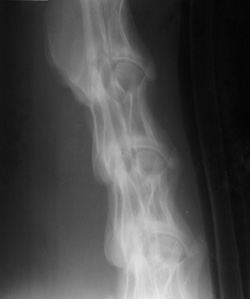

Hair in Cassette |

White artifacts due to horse hair within the cassette during exposure of the film. Plastic closer inside cassette (striped object), round balls are put on the horse neck for measurement purposes. They are on the outside of the horse. One is larger than the other. Which one?